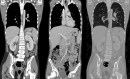

Neuroblastoma represents the most common solid extracranial tumor in children under 5, accounting for 8% to 10% of all childhood cancers. Primary central nervous system (CNS) neuroblastomas are a very rare location and only few cases are available in the literature. It was first described in 1973 by Hart and Earl as supratentorial primitive neuroectodermal tumors. Clinical presentation is highly variable and depends on the initial location of the tumor. Regarding imaging, primary brain neuroblastoma shows no pathognomonic appearance on brain computed tomography (CT) whether or not enhanced or magnetic resonance imaging (MRI). There were no standard guidelines available for the adjuvant treatment in case of primary CNS neuroblastoma. Surgery remains the main and the first tool toward these lesions. Radiotherapy associated or not to chemotherapy is offered based on patient´s age. Here, the authors report a new pediatric case of primitive central nervous system neuroblastoma revealed by an intracranial hypertension syndrome and confirmed by both histopathological and immunohistochemistry study after a gross total surgical excision. The postoperative course was uneventful and the child had good recovery.